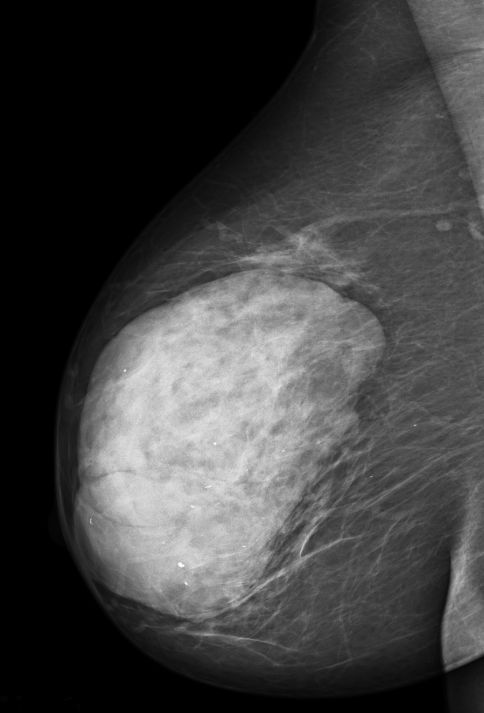

Mammographie 81-jährige Frau mit einer großen Raumforderung der rechten Brust. 9 x 4,5 cm großer, 2-knotiger, allseits gekapselter Tumor. Auf den Schnittflächen knotiges und partiell pseudozystisch umgewandeltes mit Spalträumen versehenes grau-bräunliches und grau-weißliches zäh-elastisches Gewebe. Histologisch mesenchymales Gewebe mit blattartiger Konfiguration und eingelagerten ausgeweitete, partiell komprimierte Gangstrukturen. < 4 Mitosen/10 HPF. Fibröse kapselartige Begrenzung.